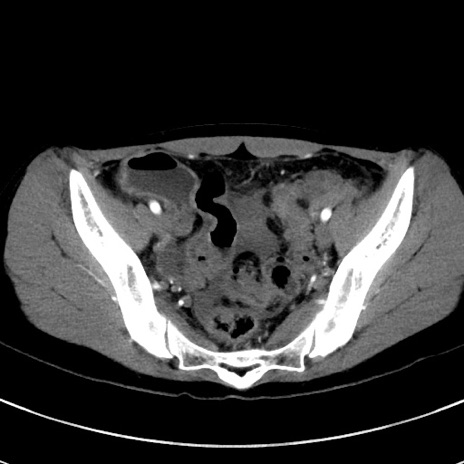

症例17(横断像)

【症例】20歳代女性

【主訴】嘔吐、下腹部痛

【現病歴】昨日夕食後に嘔吐し下腹部痛が出現。本日になっても嘔吐持続し改善しないため来院。

【身体所見】意識清明、BT 37.2℃、BP 108/67mmHg、腹部:平坦、やや硬、下腹部正中から右にかけて圧痛あり、反跳痛軽度あり、tapping pain(+)。

【データ】WBC 13600、CRP 14.94